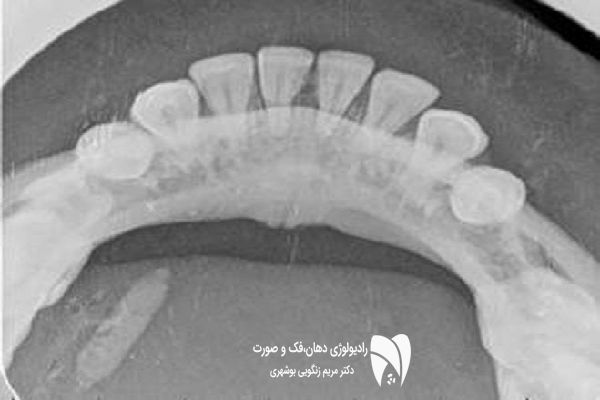

در عکاسی پرتره، هدف اصلی ثبت تمام صورت از بالای سر تا گردن در ۳ حالت اصلی است: لب ها کنار هم، دهان باز و لبخند کامل. از این نوع تصاویر برای تحلیل زیبایی و تقارن صورت استفاده می شود.